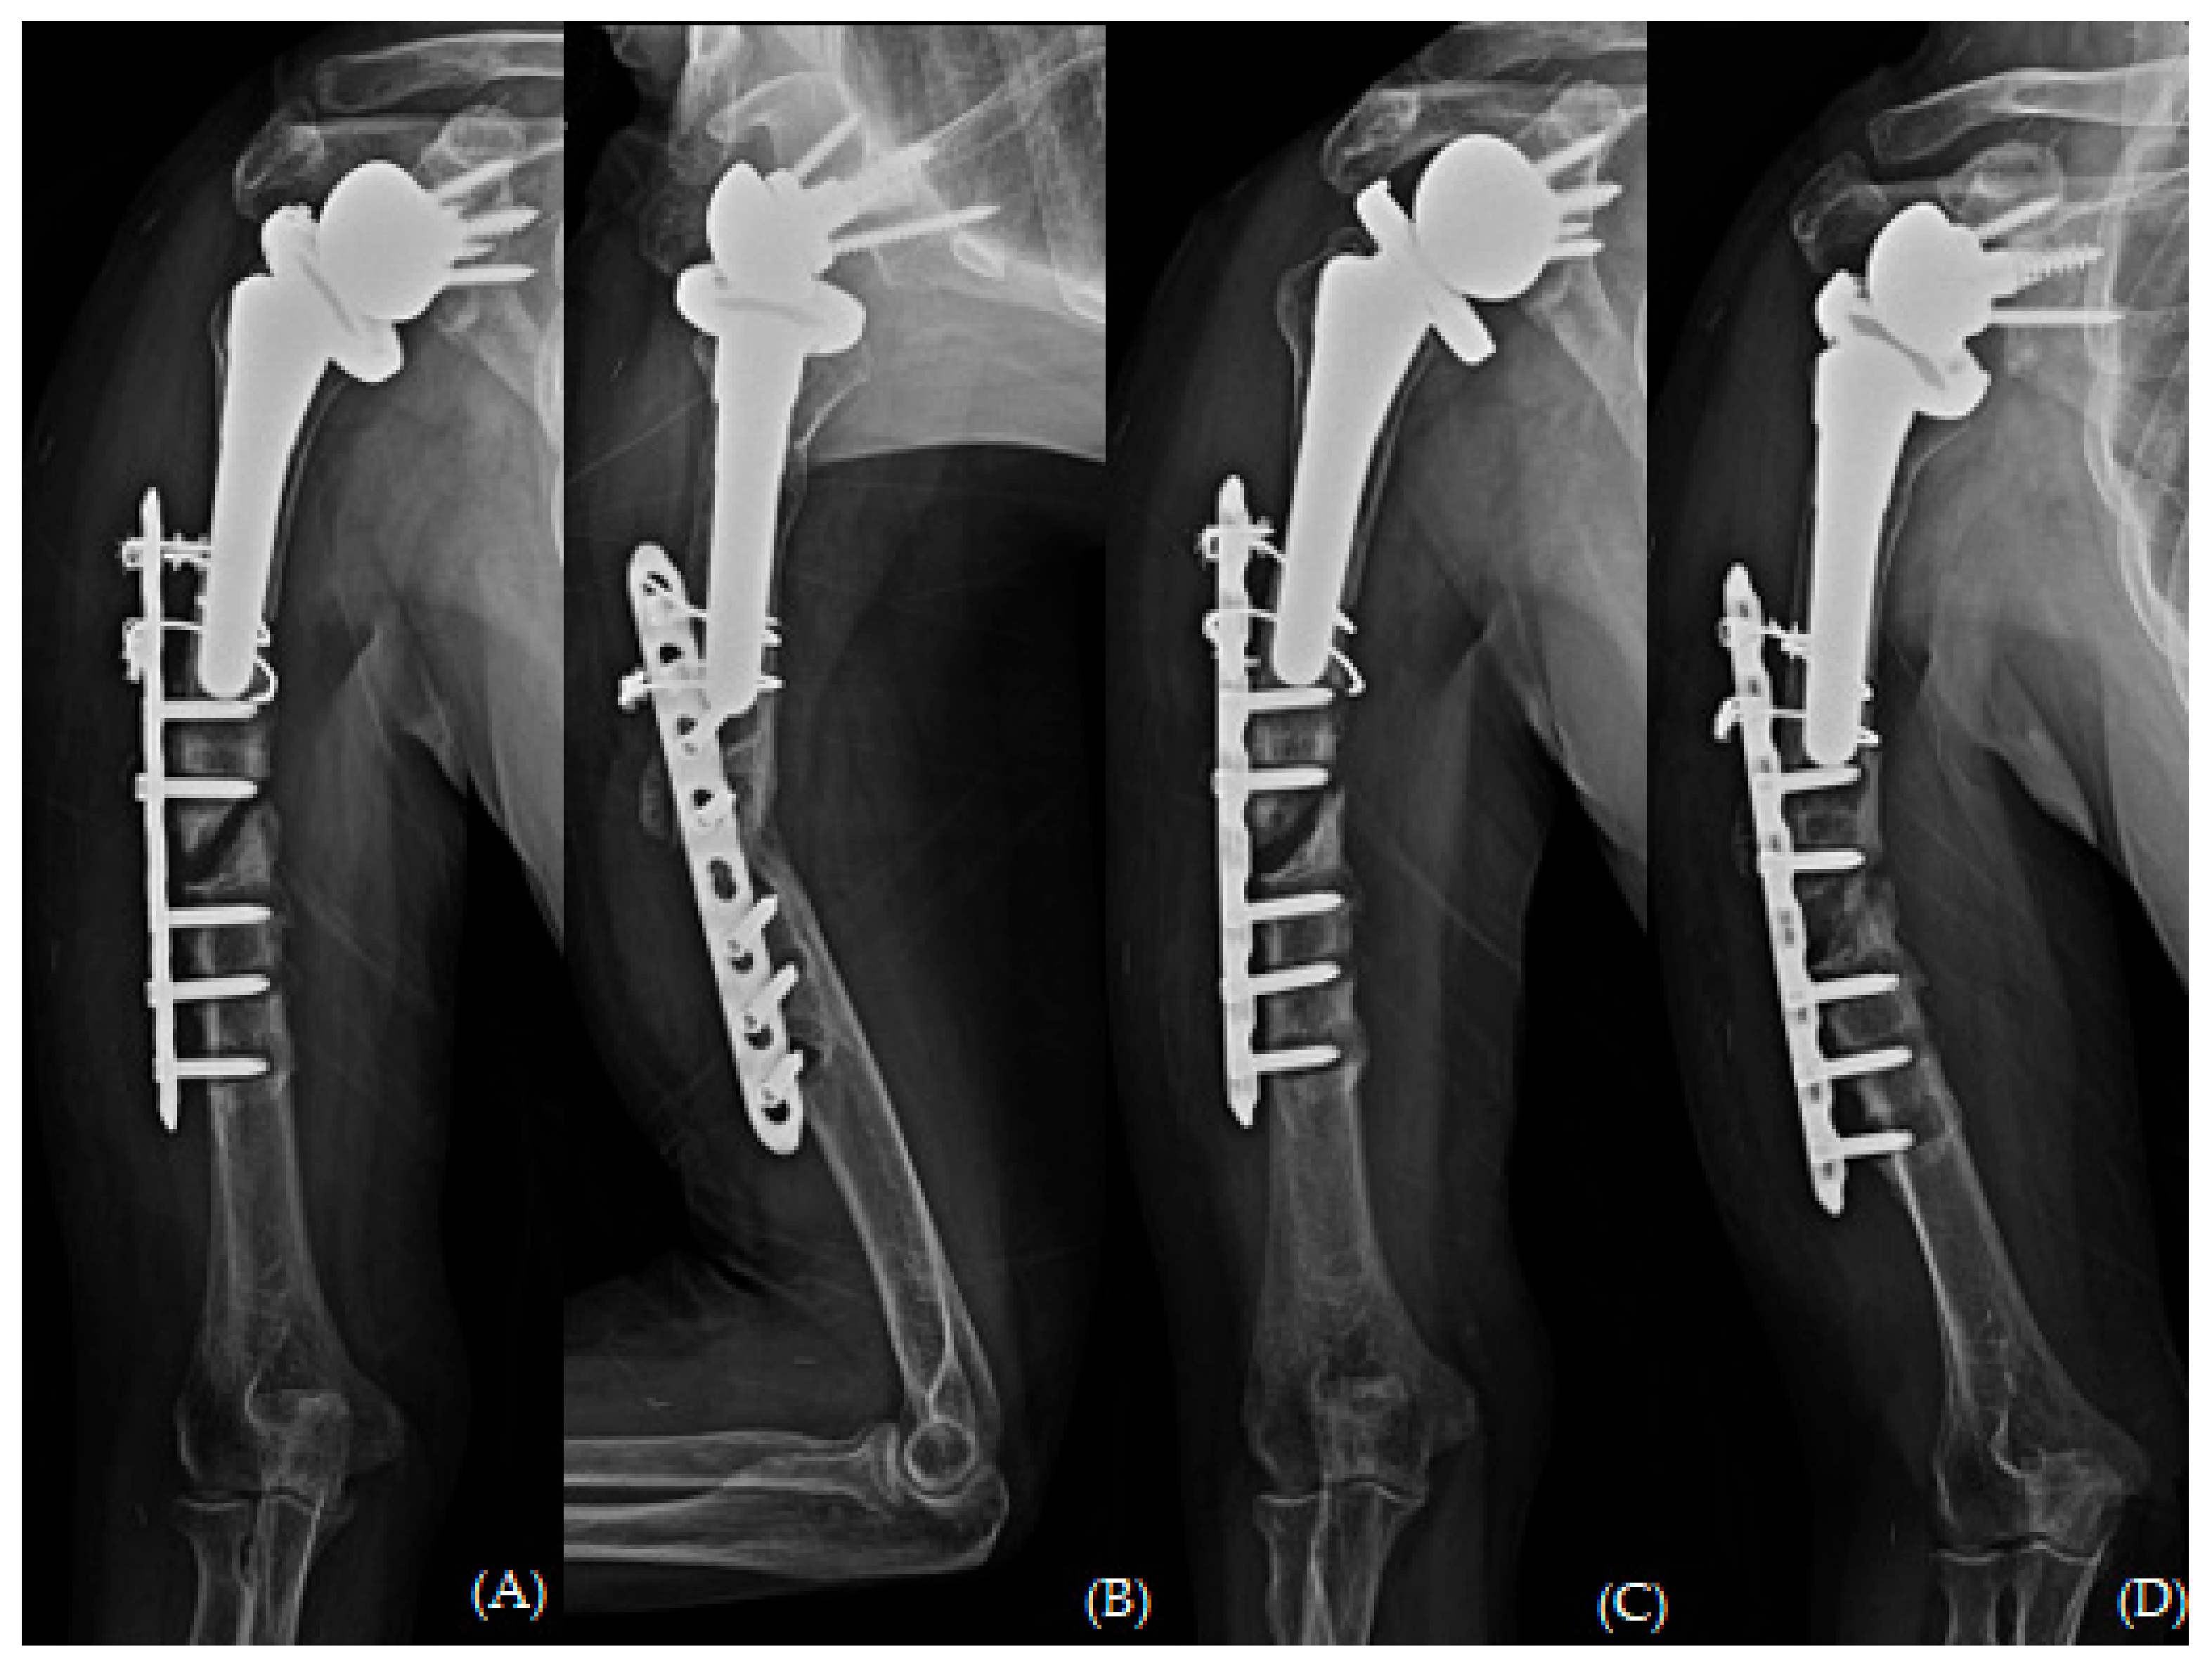

Figure 4. Plain radiographs of humerus (A) AP; (B) lateral and (C,D) oblique views 6 months after open reduction and plate osteosynthesis for periprosthetic fracture.

Upon reviewing the simple radiographs captured 3 months after the operation, we observed breakage of the proximal wires; all screws had loosened without pulling out, callus formation was absent, and varus deformity was noticeable (Figure 3). The patient was treated conservatively with an abduction brace for 6 months post-operatively. On simple radiographs captured 6 months post-operatively, the fracture site displayed bone absorption and a noticeable progression of varus angulation (Figure 4). Radiographic findings confirmed atrophic non-union, necessitating a comprehensive approach to address both stability and maintain the structure of the anatomical biology through revision osteosynthesis. In order to discern the weakness reported by the patient, a cervical spine evaluation, electromyography (EMG), and nerve conduction velocity study (NCV) were conducted, and all results were confirmed to be within normal range.